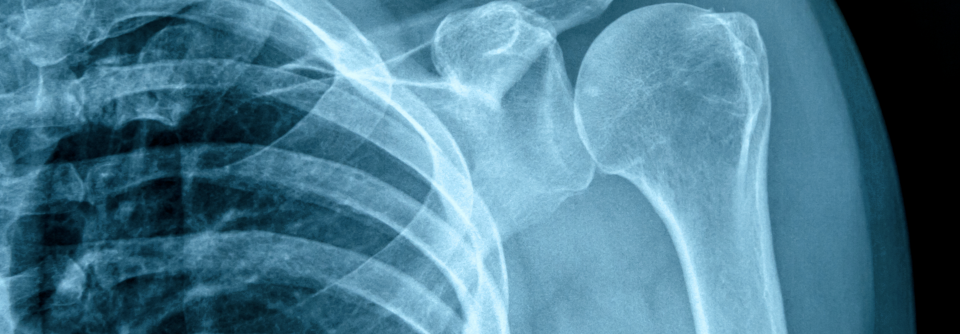

Mit einem Anteil von mehr als 95 % dominiert die anteriore Dislokation. In der Untersuchung fällt eine asymmetrische Schulterkontur mit prominentem Akromion und anteroinferior tastbarem Humeruskopf auf. Verdachtsdiagnose, Richtung der Dislokation und Begleitfrakturen der Tuberositas major lassen sich im Röntgenbild sichern (anterior-posteriore und skapulare Aufnahme).